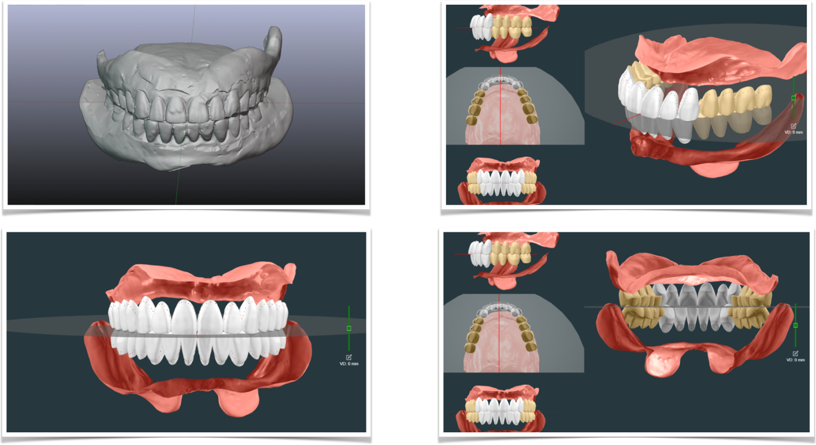

最新な入れ歯(義歯)デジタルデンチャー

現在最も新しい入れ歯(義歯)の作製方法として注目されているのが、このデジタルデンチャーになります。

デジタルデンチャーは、特徴の1つとして現在の入れ歯をコピーすることが可能となります。まだまだ改良の余地はありますが、現在の入れ歯(義歯)をスキャンして、短期間で入れ歯(義歯)を完成する事が可能となります。

入れ歯のデザイン

コンピューター上で入れ歯(義歯)をデザインする事ができます。非常に簡単にデザインができることも、デジタルデンチャーの特徴の1つになります。

デジタルデンチャーセット

完成したデジタルデンチャーです!

非常に粘膜面のコピーが上手くいっており、入れ歯の形が非常に再現されています。

デジタルデンチャー(お口の中)

お口の中でも問題なくセットができました。外形の変化が少ないので違和感が少ないと考えました。